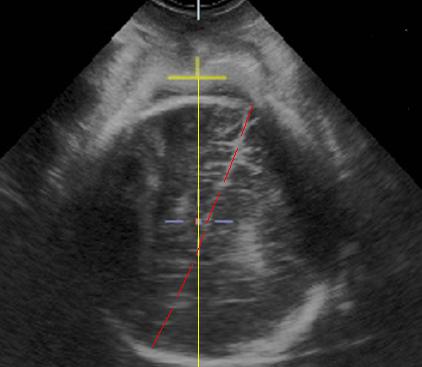

GE公司的SonoVCAD labor技术是基于三维容积超声的计算机辅助产程监测软件。利用三维超声多平面成像技术,可同时显示相交平面,增加了更多信息,使得测量的切面更为准确,重复性佳[5]。软件可在三维容积数据的不同平面自动测量出相应的胎头方向角(图1)、胎头进展角(图2)、胎头下降距离(图3)及中线角(图4)这四个参数,并在产程中动态观察各参数的变化,利用软件记录产程的全过程(图5),从而监测第二产程进展。

图3. 在A平面,点击胎头颅骨边界及先露的最外缘,胎头下降距离为从耻骨联合为起点到先露最外缘下降距离